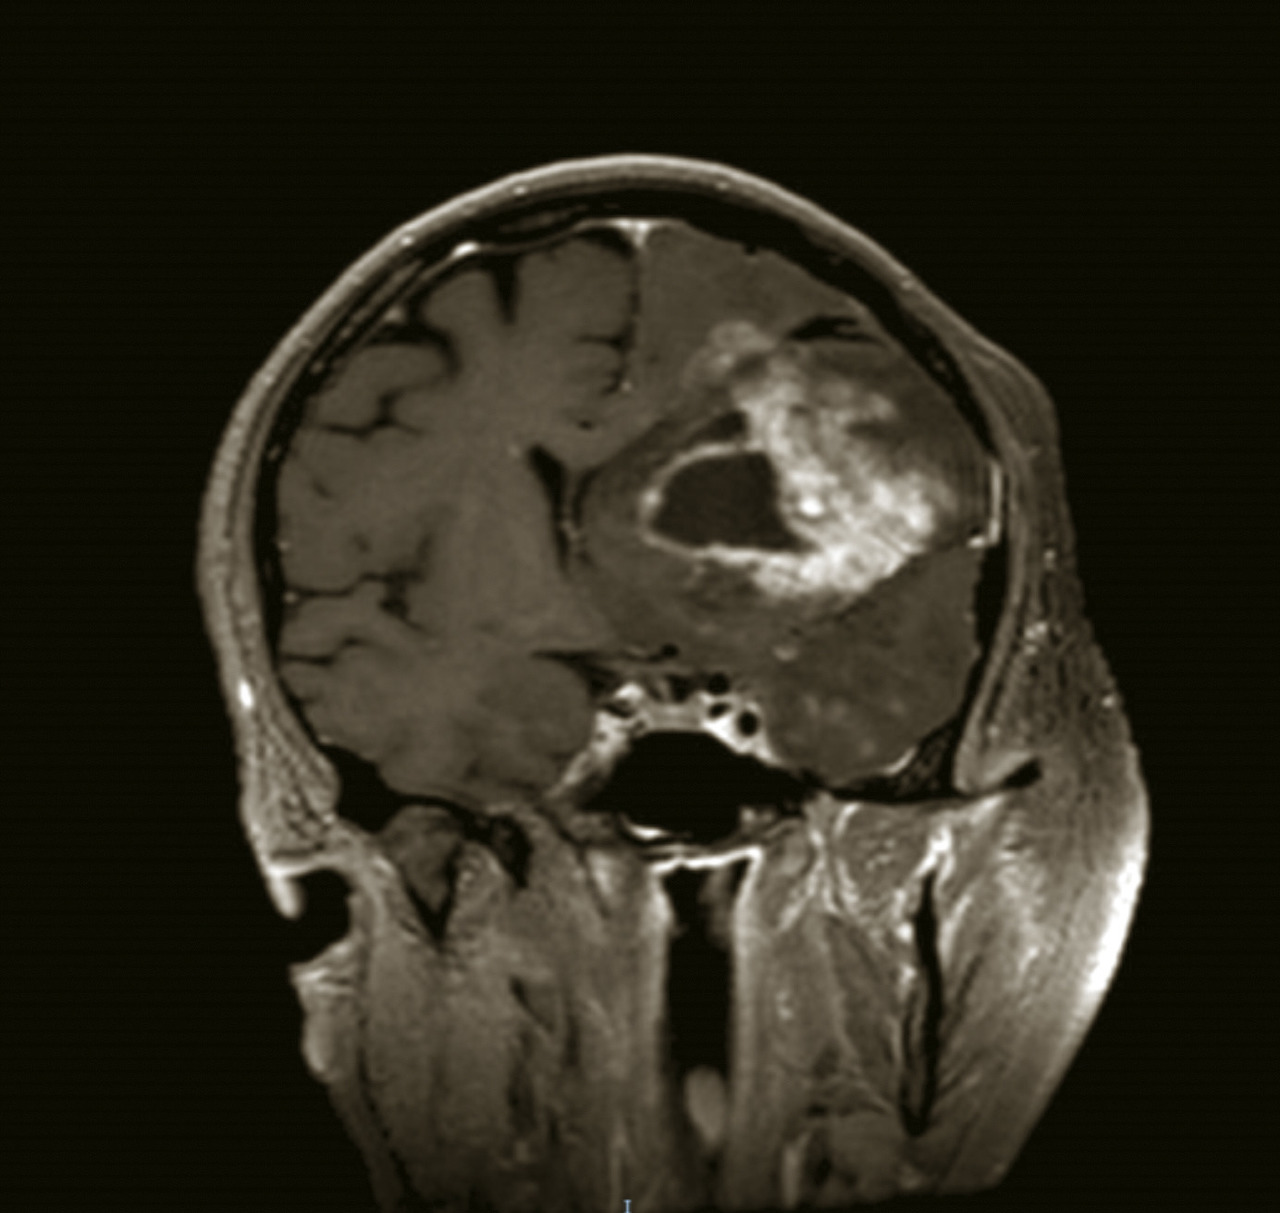

Une tumeur cérébrale peut se compliquer d’une hémorragie, favorisée par des facteurs intrinsèques à la tumeur (la néoangiogenèse tumorale dans les gliomes malins ; certaines métastases cérébrales sont plus volontiers hémorragiques, en particulier celles des mélanomes), ainsi que des facteurs systémiques (troubles de la coagulation induits par la tumeur, thrombopénie, anticoagulation à visée curative pour une phlébite ou une embolie pulmonaire, thérapies anti-angiogéniques). L’hémorragie intratumorale peut se manifester par une hypertension intracrânienne, un déficit focal d’installation aiguë ou la majoration d’un déficit déjà connu, une crise d’épilepsie. Elle peut être aussi asymptomatique et diagnostiquée à l’imagerie. Elle apparaît au scanner non injecté sous la forme d’une hyperdensité spontanée et à l’IRM non injectée par un hypersignal en T1 (fig. 8) et en hyposignal en T2* au sein de la tumeur.